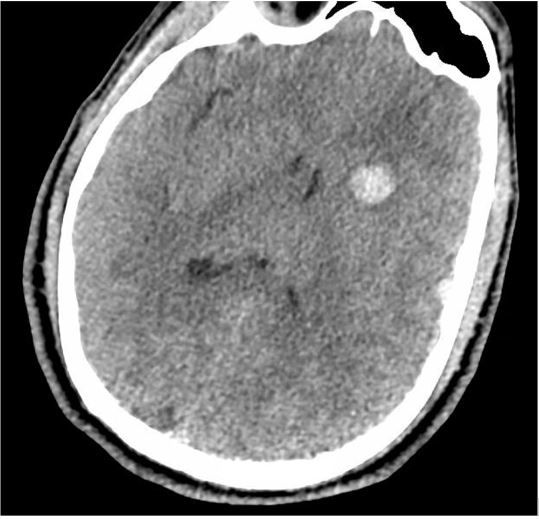

Initial diagnostic imaging (CT head, below)

(CT of patient's head obtained in emergency department)